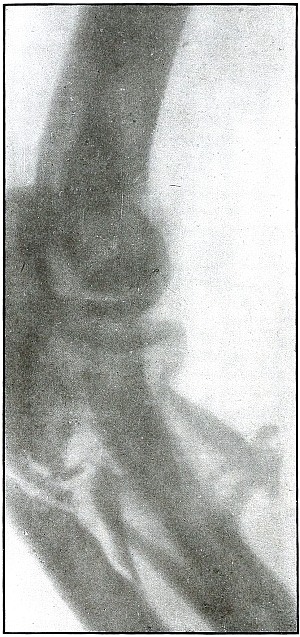

Plate 20.

[Pg 51]

Rifle—Plate 20.

UPPER EXTREMITY.

Gunshot Fracture of the Elbow.

Wound of entrance, posterior aspect of forearm internal to and below

the olecranon.

Wound of exit, external border over head of radius.

The course of the bullet was diagonally anteroposterior from within

outward, striking the posterior border of the upper end of the ulna

and passing through the head of the radius, carrying the fragments

of the latter before it and lacerating the wound of exit. The energy

of impact also fissured the upper end of the shaft of the ulna and

fractured the neck of the radius without detaching the large fragments.

This is the effect of a rifle bullet at short range, or possibly a

ricochet shot at mid range.

The emergency treatment is antiseptic dressing with splint

immobilization.

The subsequent treatment is conservative, whether the wound is clean

or infected. The course of treatment of such an infected wound might

extend from four to six months.

Note.—As the

soldier always escapes the burden of explanation when the wound of

entrance is anterior rather than posterior, it should be remembered

that the forearm may occupy positions in relation to the body which

exposes the anatomically posterior aspect of the forearm to missiles

directed toward the anterior surface of the body; and as the wounds of

the forearm herein presented are described in the anatomical position,

there is no justifiable impeachment of the soldier’s valor in an

inference that he was shot from behind when the wound of entrance

involves the posterior aspect of the forearm.

[Pg 52]